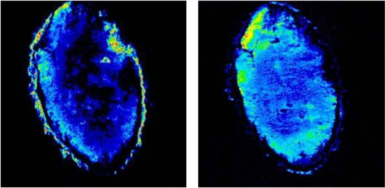

- マウスの癌における血管新生の様子

約5mm程の癌の血管透過性マッピング

青>黄>赤>白 の順に透過性が大きくなっています。 - 脳梗塞ラットのfMRI